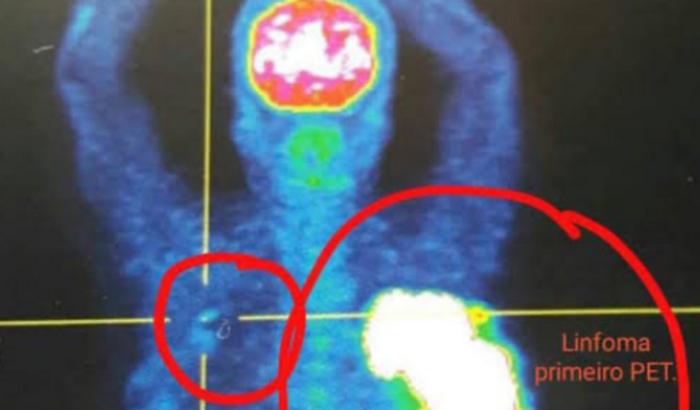

Me Chamo Eduardo, tenho 35 anos Pi de 3 meninas lindas, Filho da Márcia de 57 anos; Recentemente recebi uma das Piores notícias possíveis, “MINHA MÃE ESTÁ COM CÂNCER“ corremos, fizemos exames, ela ficou internada um período, porém é tudo muito caro só 1 Exame que ela realizou custou mais de R$:4.000,00 ( Pet Scam ) Acabei com a Reserva que tínhamos, porém ela identificou alguns Linfomas Malignos ( Passíveis de remoção Cirúrgica.